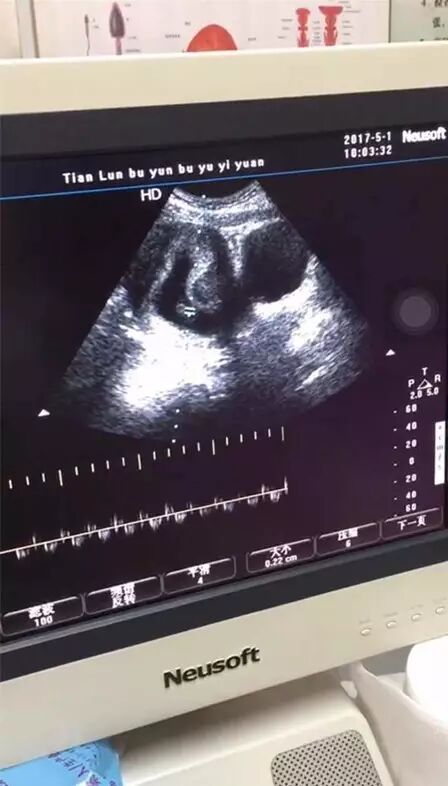

山西运城高女士(化名),昨日经B超显示已经怀孕。得知这个好消息,高女士不禁喜极而涕,这一路走来太过不容易,为了要一个宝宝,其中的付出也只有自己清楚。

后来经朋友的推荐,她来到太原天伦不孕不育医院找到谭怀敏主任进行治疗,经过全面的检查,谭主任确诊为内分泌性不孕,并确定高女士具备自然受孕的条件。随后,经过专家会诊为高女士制定了个体化诊疗方案,综合治疗对身体内分泌及整体孕育环境进行了科学调理,并监测排卵,目前已经怀孕59天。

(高女士B超显示结果)